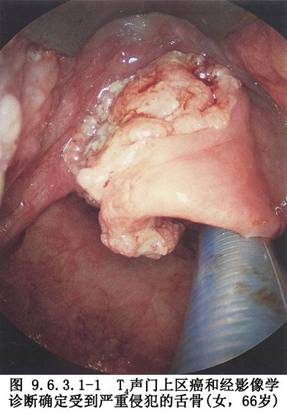

1.聲門上癌 ①T3~T4;②聲帶已固定;③會厭室帶癌並侵犯聲帶;④侵犯甲狀軟骨或環狀軟骨;⑤侵犯雙側杓狀軟骨;⑥穿出會厭前間隙;⑦侵犯會厭谷達舌根(圖9.6.3.1-1)。